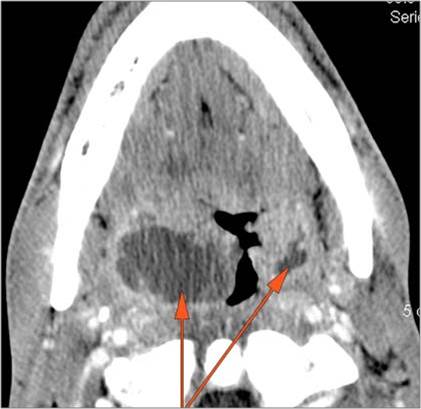

There is edema/abscess within the fat of the adjacent parapharyngeal and retropharyngeal spaces. [Yes/No]

There is excessive enhancement or thickening of the fat or other soft tissues within or surrounding the buccal space, masticator space, floor of the mouth, submandibular space or the adjacent superficial fascia or subcutaneous fat and skin. [Yes/No]

There is edema/abscess within the fat of the adjacent parapharyngeal and retropharyngeal space. [Yes/No]